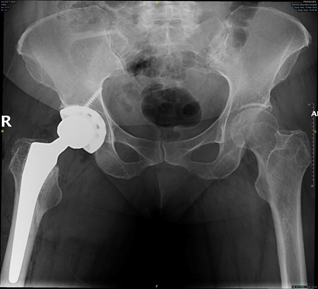

There are many skeletal abnormalities that affect hip joint and femur in sickle cell disease patients, including abnormal shape of femur metaphysis with thin cortex, decreased bone density, and medullary hyperplasia. Irregular sclerotic areas in the bone obliterate canal of the femur and finally loss of congruency of the hip joint.7 Thin femoral cortical lining inside the outer cortex sometimes gives appearance like femur within a femur (Figure 1).8

Total hip Replacement (THR) has become the treatment of choice in SCD patients with end-stage hip osteoarthritis resulting from symptomatic AVN. Patients are active young individuals at the time of surgery, that increase the risk of hip implant failure than those individuals having THA for primary osteoarthritis (OA).5 Rates of implant failure have been reported in early studies with arange from 30% to 60% in less than 5 years. This occurs often due to high functional demand of patients leading to failure of implant.9 More recent data showed improvement in survivorship of hip implant, but still overall complications are higher in sicklers relative to those individuals having THA for primary OA.10 Due to the skeletal abnormalities and medical conditions associated with SCD patients having THA, it is very important for the surgeon to understand the expected pre and postoperative course and also intraoperative considerations regarding these patients and how it can differ from patients having THA for primary OA (Figure 2).

Harris Hip Score (HHS) was used for assessment of the functional outcomes. Follow up has been done to all patients after 6 weeks and then after 6 months to determine functional outcomes by clinical examination and by X-rays. Xrays were checked for any evidence of implant loosening, dislocation, or heterotopic ossification. Patients were seen by a hematology doctors and the study authors at every follow-up visits, and we documented medical and surgical complications. Failure was defined as the need for redo hip replacement surgery due to infection, dislocation, loosening, or surgical complications (Figure 5).